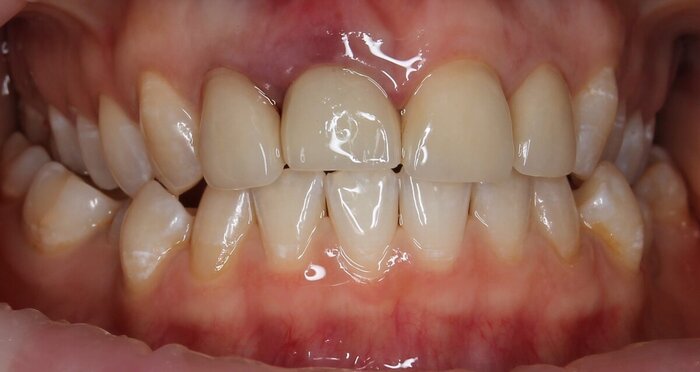

Коронка временная лабораторная. Зуб 1.1.

Кажется, для временной коронки выглядит очень органично и симпатично. Главное -функционально.

Как я уже писала выше, возможно придётся дополнительно проводить пластику мягкими тканями - деструкция кости была значительной для этой зоны зуба 1.1.

Встречаемся на снятии швов через 2 недели, а после - только через 4 месяца. Будем оценивать ситуацию и решать вопросы насущные с пластикой и/или постоянной коронкой.